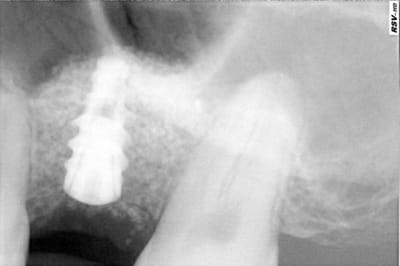

Je ne sais plus qui demandais, voici une image à 6 mois d'un lift au kasios, controle après pose du clou